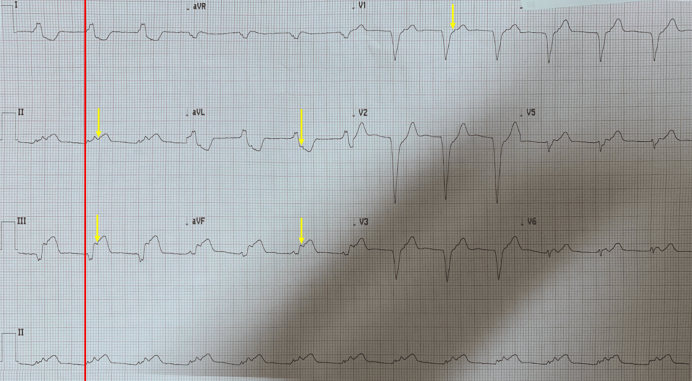

Синусовая брадикардия в 16 лет

БПВЛНПГ на ЭКГ

P pulmonale на ЭКГ 25 мм

Девиация St на ЭКГ

Низковольтажная ЭКГ

Брадикардия фибрилляция предсердий на ЭКГ

Депрессия сегмента St по передней стенке